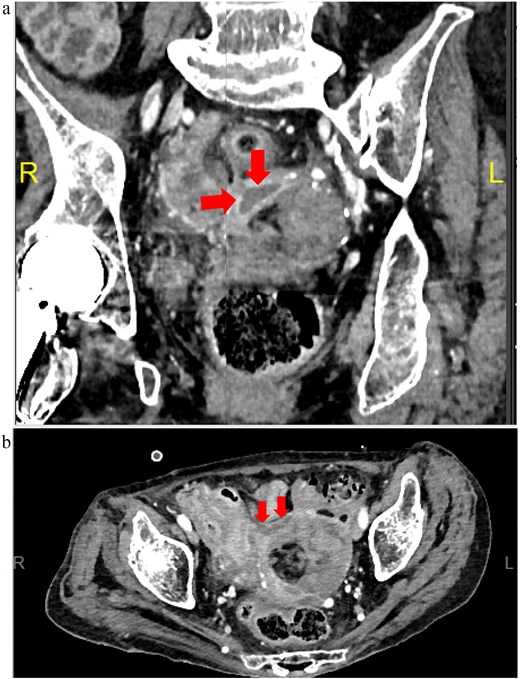

Meropenem was administered postoperatively and later de-escalated to ampicillin/sulbactam based on culture results, which identified anaerobic organisms. Inflammatory markers gradually improved, and initial drains were removed. Although inflammation persisted mildly, follow-up CT on postoperative Days 3 and 10 showed no abscess formation. On postoperative Day 18, fever recurred, and CT revealed a pelvic abscess (Fig. 4). Transvaginal drainage using a Nelaton catheter aspirated 2.3 mL of purulent fluid, resulting in clinical improvement. Antibiotics were discontinued on postoperative Day 31. No additional surgery was required, and the patient was transferred to a long-term care facility.

Postoperative Day 18 contrast-enhanced CT images (equilibrium phase). (a) Coronal view; (b) horizontal view.